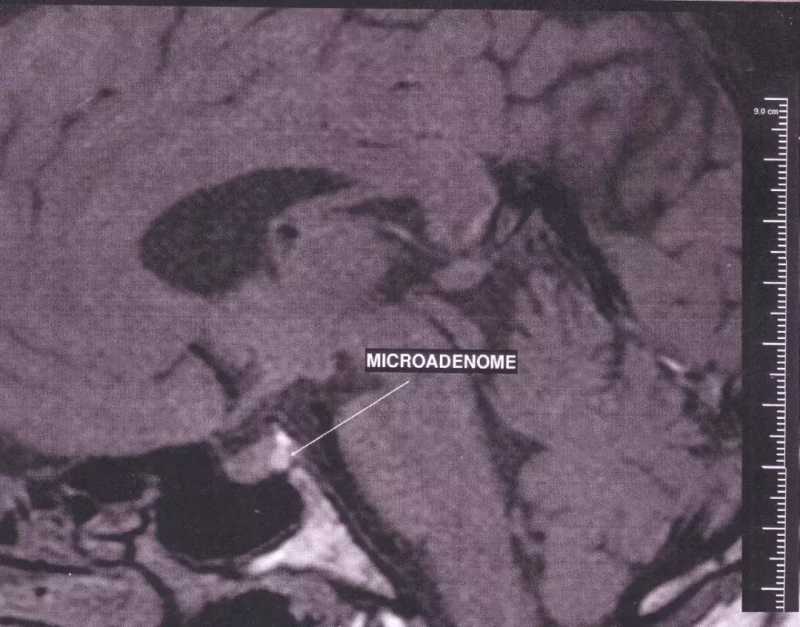

经过医生的全面检查,大家才终于知道这位小男孩为什么成长得如此迅速。

使小罗伯特疯狂生长的秘密,正埋在他的大脑里。

他被检查出了患有垂体腺肿瘤,并被确诊为巨人症。

垂体又称为“脑下垂体”,是大脑底部水滴状下垂的结构。

只有一粒豌豆那么大,但它却能分泌出与人类身体生长最密切相关的激素——生长激素(growth hormone)。

其功能包括促进身体组织的生长,使体内细胞的数目增加及变大,使身体各部分组织器官变大等。

若脑下垂体发生异常,就有可能引发生长激素的分泌异常。

分泌过少,会引发侏儒症。分泌过多,则会引发巨人症。

其中,引发生长激素分泌过旺的最常见原因,便是脑下垂体腺瘤。

而发生在罗伯特身上的巨人症,正源于这种垂体腺瘤。

如今,已有一些医疗手段可应用于处理垂体腺瘤,如手术或药物治疗等。

只要发现得早,侏儒症和巨人症等原发于垂体异常的疾病,都可以得到缓解。